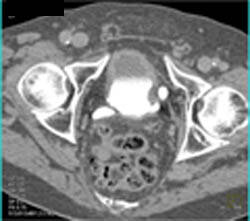

Bladder Calculi